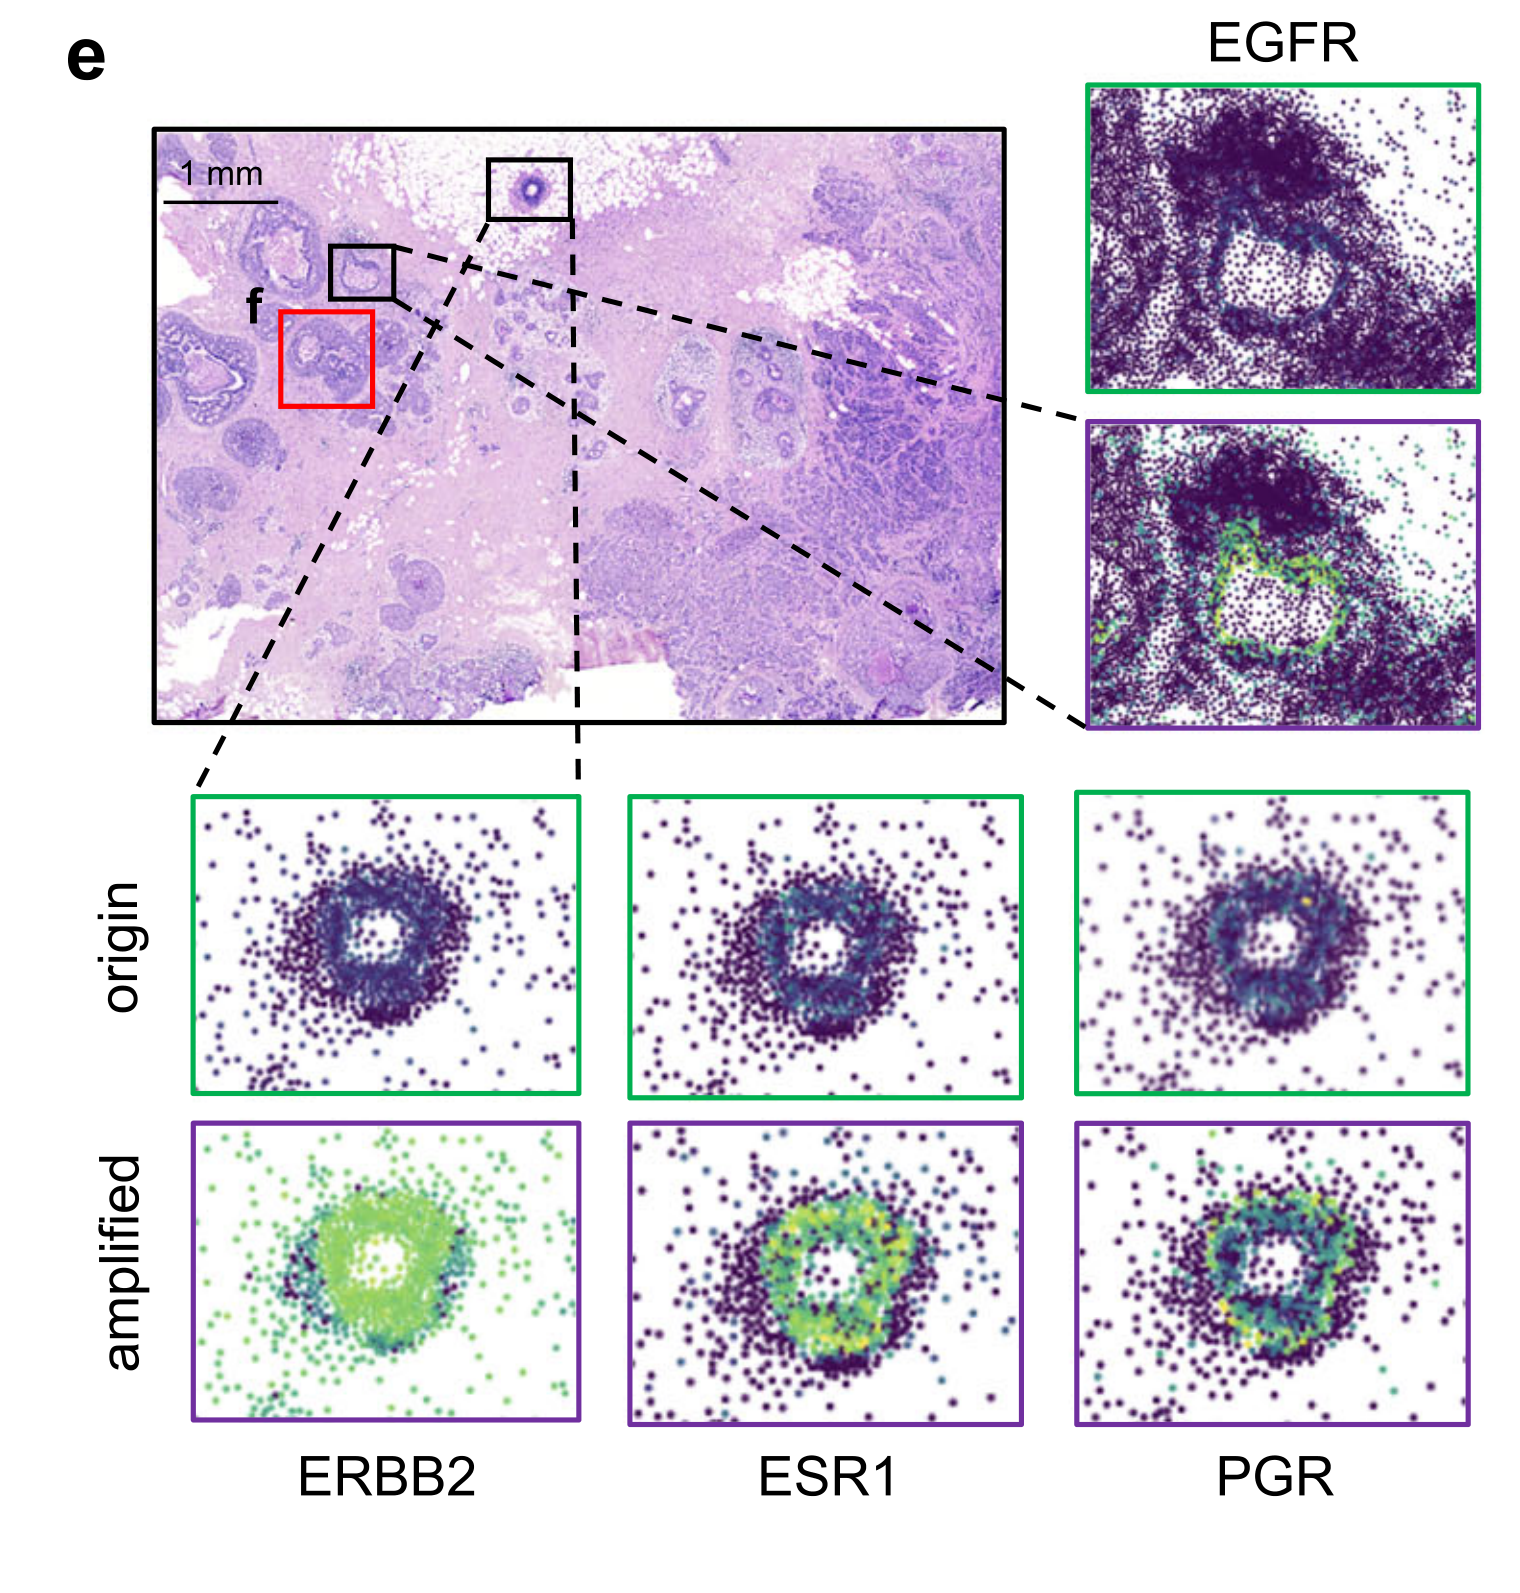

Gong Y. et al. - 2025

Unveiling fine-scale spatial structures and amplifying gene expression signals in ultra-large ST slices with HERGAST

Condition Dimension

N/A

Data Components

Biological AnnotationGene Expression Matrix

Data

Metadata

None

Modality

Imaging-based

Resolution of observation

Cellular

Visualized Elements

Observation

Biological

Tissue

Abstraction

Partial

Chart Type

Scatterplot

Communicative/Contextualization

None

Comparative Design

None

Layout

Spatial : Physical

Scalability Strategy

None (Item-level)

What spatial tissue architecture is present in a diseased tissue sample?